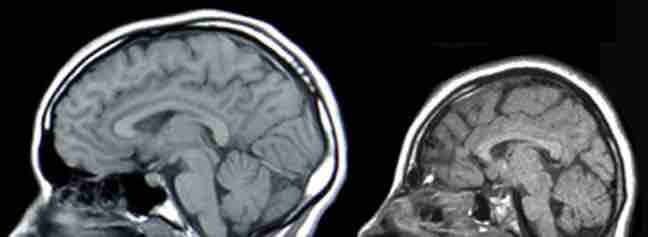

Microcephaly

MRIs of a normal individual (left) and a patient with microcephaly (right).

• In humans, microcephaly is the only proven malformation, or congenital abnormality, found in the developing human fetuses present during the Hiroshima and Nagasaki bombings.

A neurological disorder which causes the affected person to have an abnormally small head due to a failure of brain growth.

In humans, microcephaly is the only proven malformation, or congenital abnormality, found in the developing human fetuses present during the Hiroshima and Nagasaki bombings. No statistically demonstrable increase in congenital malformations was found among the later-conceived children born to survivors of the nuclear weapons at Hiroshima and Nagasaki. Surviving women of Hiroshima and Nagasaki—even those exposed to substantial amounts of radiation—had children with no higher incidence of abnormalities than the Japanese average.